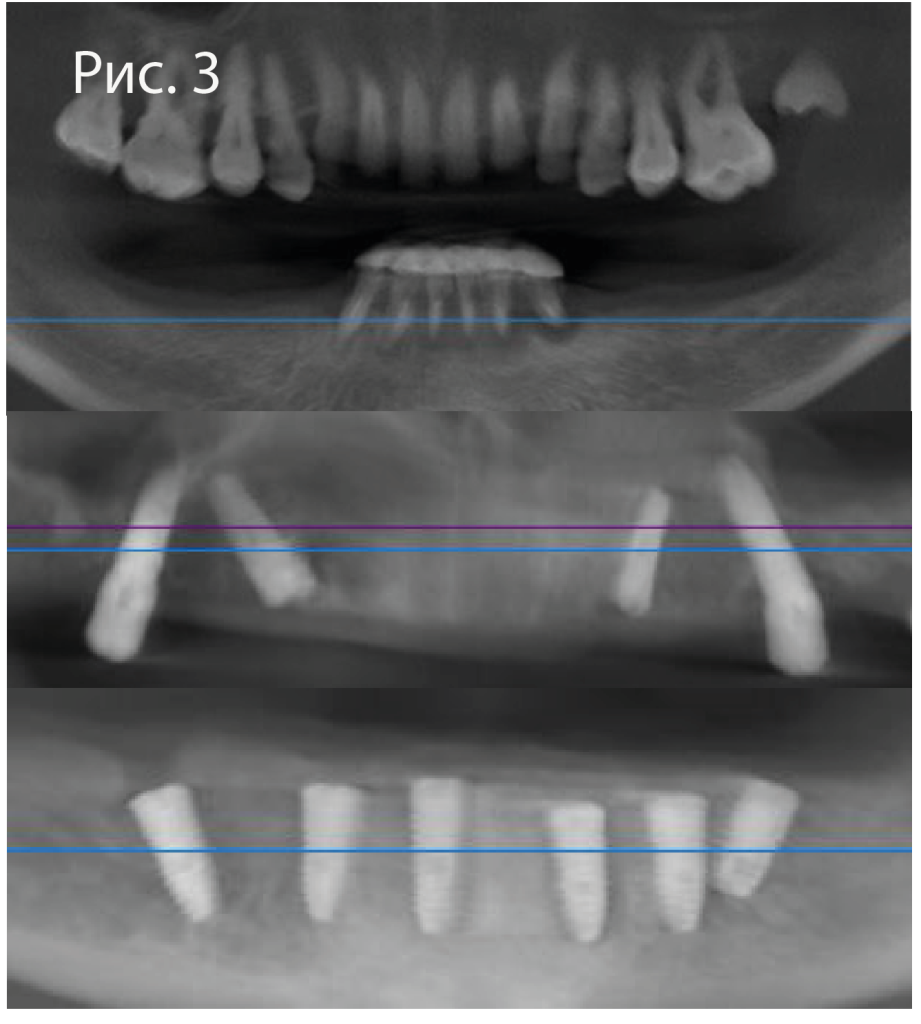

3.png

Данные интраорального сканирования и КТ сопоставляются в программе Implant Studio (3Shape). На верхней челюсти в качестве ориентира используются 6 зубов, на которые также будет опираться хирургический шаблон. На нижней челюсти с этой целью наносят текучий композит на шляпки ортодонтическоих винтов Osstem.